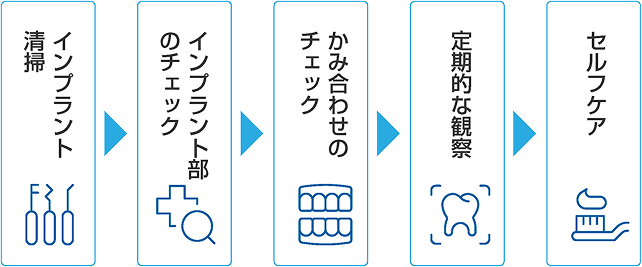

インプラント周囲炎を防ぐために

インプラント治療後のメンテナンスは「天然歯以上に重要」といわれています。

当院ではインプラント治療の経験豊富な歯科医師と、

研鑽を積んだ歯科衛生士がチームが以下のようなメンテナンスを行っています。

インプラントメンテナンスの流れ